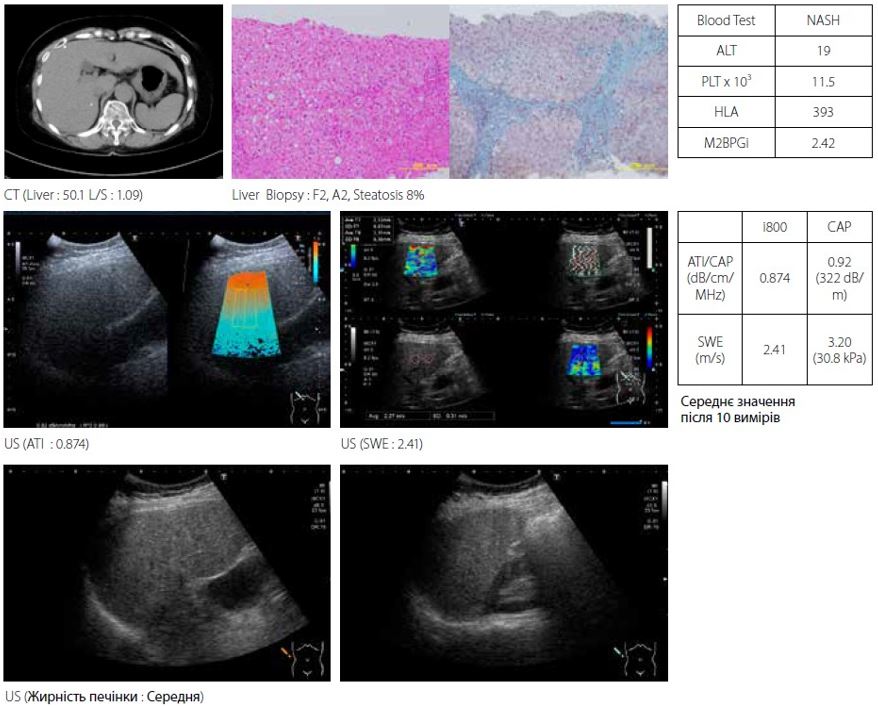

Коли цироз печінки прогресує, ступінь стеатозу зменшується. Випадок 2 — затухаючий НАСГ у 60-річної жінки (рис. 7). НАСГ прогресував до цирозу печінки з очевидним посиленням фіброзу. При біопсії печінки у пацієнта діагностовано F4 і стеатоз 8%. Для повного обстеження висвітленого НАСГ необхідно належним чином обстежити як фіброз, так і стеатоз.

Малюнок 7 Випадок 2: 60F з підвищеною ехогенністю через НАСГ